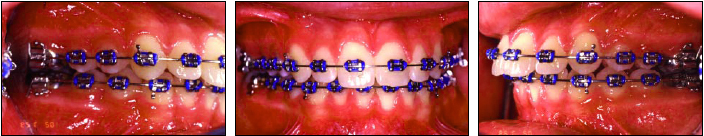

A functional Class I occlusion was obtained in both patients, with ideal overbite and overjet (Fig. 6, Fig. 12). The coincident midlines were maintained, and both skeletal and soft-tissue discrepancies were improved. Most important, both patients' chief complaints were corrected, and our primary treatment objectives were met.

Fig. 6 Case 1. After 23 months of treatment, note improved soft-tissue profile, Class I molar and canine relationships, coincident midlines, and ideal overbite.

Fig. 12 Case 2. After 24 months of treatment, note orthognathic soft-tissue profile, Class I molar and canine relationships, coincident midlines, and ideal overbite.